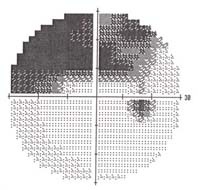

Visual field test The visual field gray-scale printout (left) corresponds to this kind of optic nerve damage. Visual field tests assess your peripheral vision. Early damage from glaucoma can often be detected by this test. Dr. Shimokaji uses the latest computerized technology to assess peripheral vision. Currently she is using primarily the Humphrey SITA 24-2 test. Both eyes are tested in 10 to 20 minutes and the visual field examination is usually repeated annually to monitor for progression of glaucoma damage. Once we have several reliable studies on a given patient, the glaucoma progression analysis ("GPA") software analyzes your visual field tests to determine whether your disease is stable, possibly worsening or getting worse.